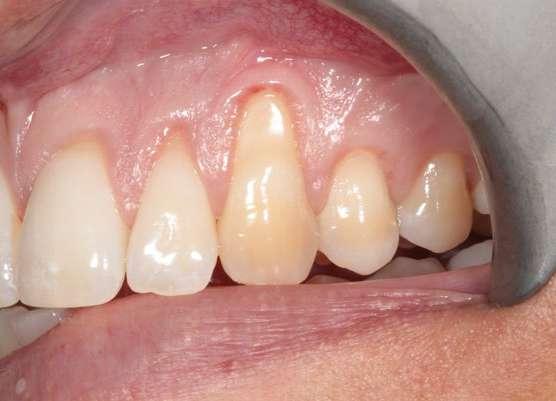

En la exploración clínica observamos recesiones gingivales múltiples en maxilar superior combinado con erosión de la encía y ligero desgaste cervical que borra la línea amelocementaria (Fig. 1). El sondaje periodontal en todos los dientes fue inferior o igual a 3 mm y no se detectaron puntos de sangrado al sondaje. Los dientes 1.3 y 2.3 mostraron ≤ 1 mm de encía queratinizada apical a la recesión. Cabe también destacar la rotación del incisivo lateral superior derecho (1.2). El principal factor etiológico de sospecha en este caso fue el cepillado agresivo.

Figura 1: Situación inicial. Obsérvese la recesión gingival profunda en 1.3 y 2.3, así como la erosión gingival y el borrado de la línea amelocementaria debido al cepillado agresivo.